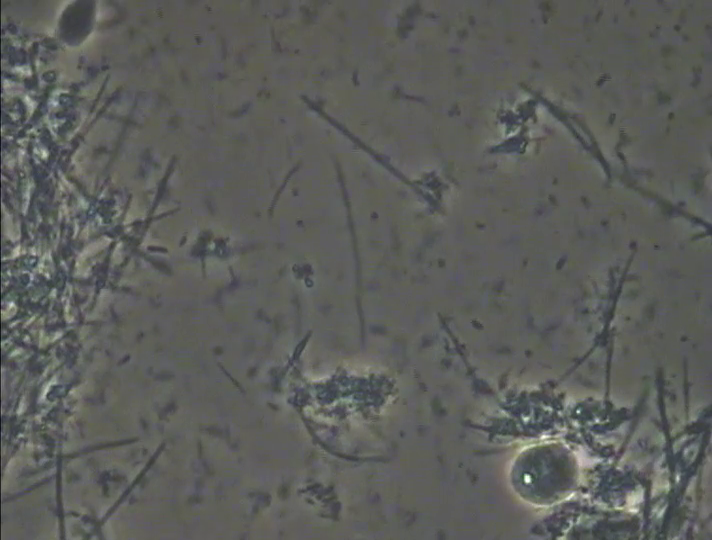

そこで、Nさんに説明をしてカウンセリング(歯周病のPCR検査や口臭検査、マイクロスコープを使用した口腔内の細かい所までの診療)に変更させていただきました。